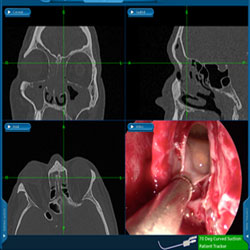

These sinuses in particular remain the most difficult to treat surgically because of their location and complex anatomy. You may need to have a CT Scan to help your ENT physician determine the most effective course of treatment. Symptoms of frontal sinus disease can include:

There are a variety of surgical techniques that have been developed to treat the frontal sinuses, including anterior ethmoidectomy, balloon sinuplasty, endoscopic frontal recess dissection, and more advanced endoscopic and external techniques. The surgical technique used to treat the frontal sinus is usually dictated by the specific disease affecting the sinus, and will be discussed with you prior to surgery. Your ENT physician will be happy to discuss these surgical options and answer any questions you may have.